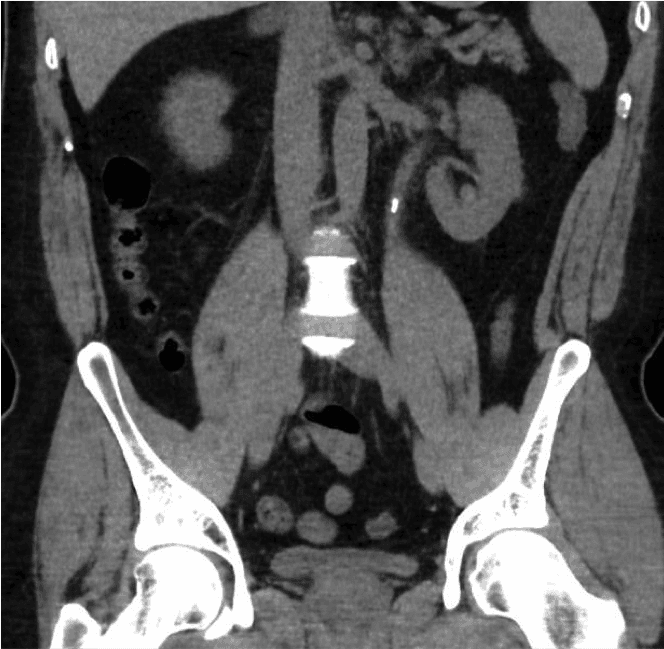

Initially a urine dipstick test will be preformed to check for blood in the urine and rule out urine infection. Blood tests for kidney function and Calcium are performed. The definitive diagnostic test for stone is a plain CT scan of the Abdomen (CT Kidney Ureter Bladder area or CT KUB). This will show the size and position of stones which will help in planning treatment.